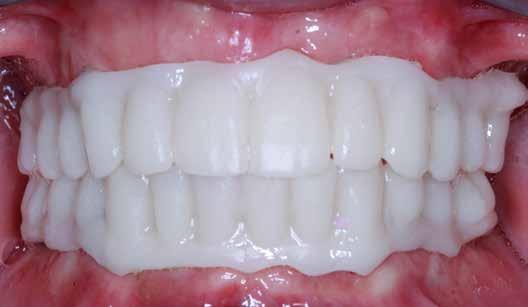

Ebben a cikkben egy 16 éves lánypáciens esetét szeretném bemutatni (1–7. képek)

A fix fogszabályozó készülék mindössze 16 hónapos kezelés után került eltávolításra! Páciensünk legnagyobb örömére állcsontműtét nélkül sikerült mind az arcesztétikai, mind a funkcionális rehabilitáció (13–18. képek)